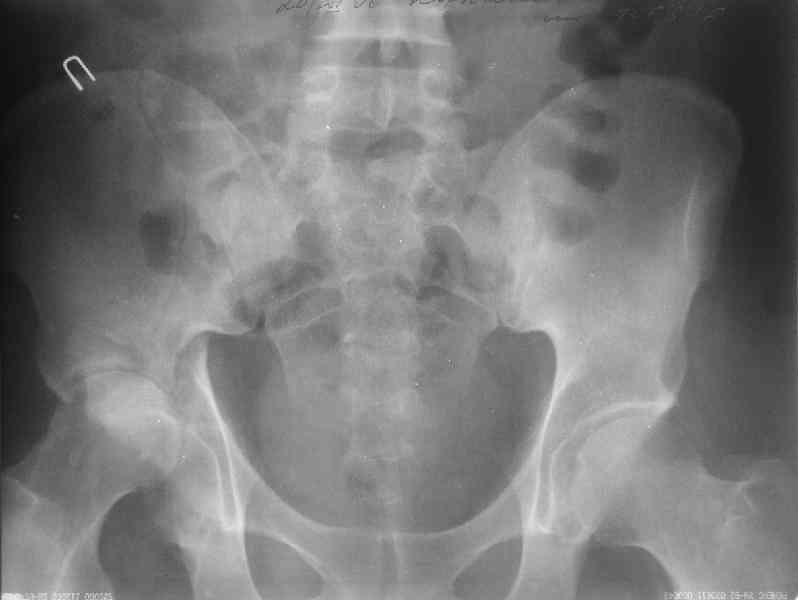

Уважаемы коллеги! Поступил непростой больной 24 лет через 1 месяц после травмы (фото в приложении). Кроме перелома правой вертлужной впадины, перелома и вывиха этого же бедра имеются переломы диафиза правой плечевой кости, диафиза правой локтевой кости, диафизов обеих костей левого предплечья.

Неврологии со стороны нижних конечностей нет. Планируем первым этапом выполнить ЗИМО длинных трубчатых костей. Вопросы: 1. имеет ли смысл в эти сроки идти на остеосинтез вертлужной впадины и вправление вывиха или планировать первичное эндопротезирование? 2. Есть у кого-нибудь ссылки или другая информация по поводу исходов лечения переломов вертлужной впадины, сопровождающихся вывихом головки бедра в разные сроки (буду очень признателен, если поделитесь)?A male 24 y.o, admitted to our unit today 1 month post injury - images attached. Except ipsilateral acetabular fx, femoral shaft fx and hip dislocation also he has shaft fxs of right humerus and ulna, left radius and ulna. No neurological deficits after the hip dislocation. At first we plan closed nailing of all long bones. Questions are regarding the acetabular fx + dislocation. With the 1 month of exposition and obvious callus everywhere does it make sense to attempt ORIF of the acetabulum with hip reduction, or primary THA should be considered? Does anybody have references on outcomes after delayed surgeries for acetabular fx + hip dislocation depending on duration of the delay? С уважением Максим Агалаков, УНИИТО Е-бург.

Now, to my own opinion. I believe that this is a Transverse + Posterior wall fracture type.

The transverse element does not seem so much displaced, and now after 1 month I believe it will be extremely difficult to mobilize and reduce. So I suggest you get a CT to check for incarcerated fragments, a high possibility in this unreduced dislocation. Then you open posteriorly, Kocher Langenbeck, with the patient prone, extract any incarcerated frgments, reduce the hip, fix the posterior wall by screws, and then apply a contoured reconstruction plate from the iliac wing to the ischium. This plate will hold the ransverse element, as well as buttress the posterior wall fragment(s).